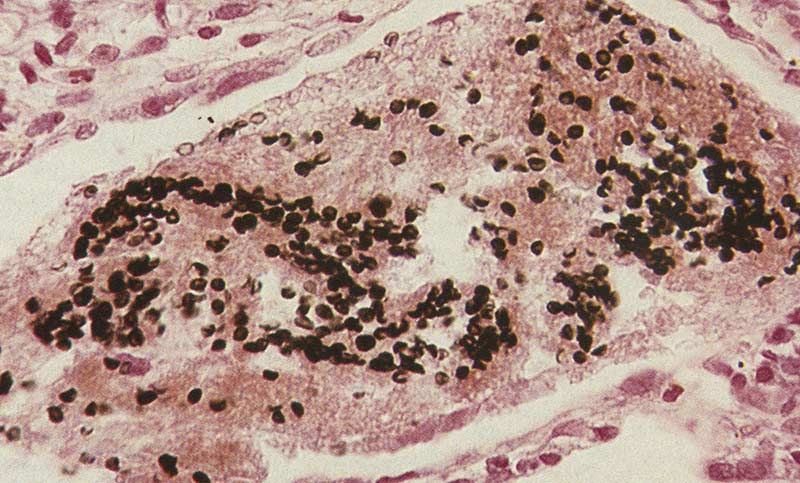

Рентгеновские снимки при пневмоцистной пневмонии